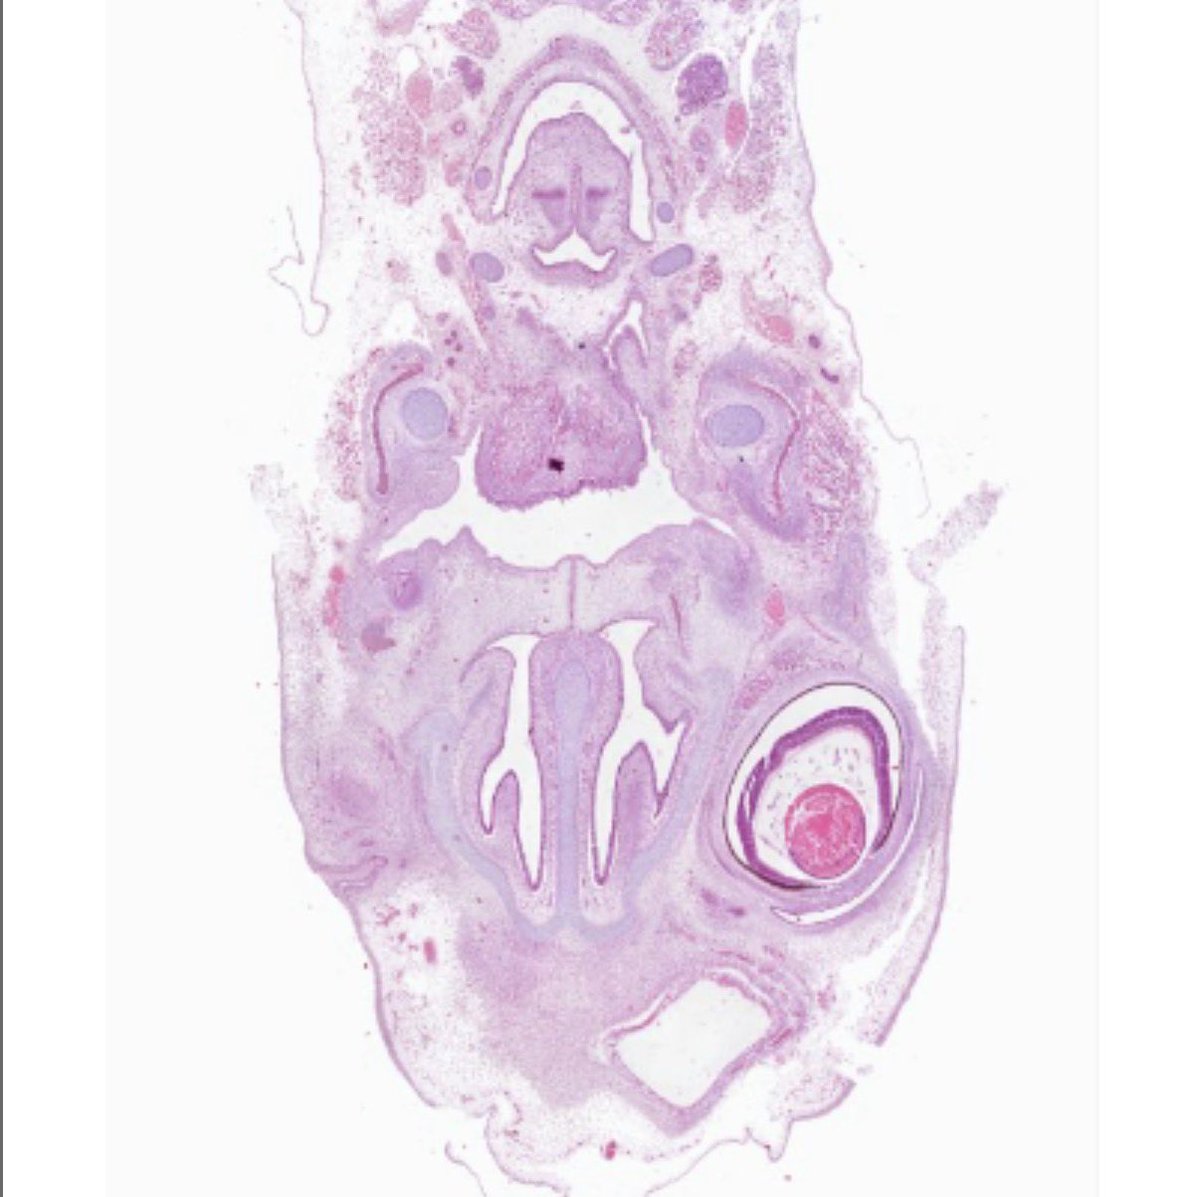

Microscopio Virtual - Histología y Embriología @histoemb , Facultad de Medicina, Universidad de la República, Uruguay. Desarrollado por @ernestomiquel